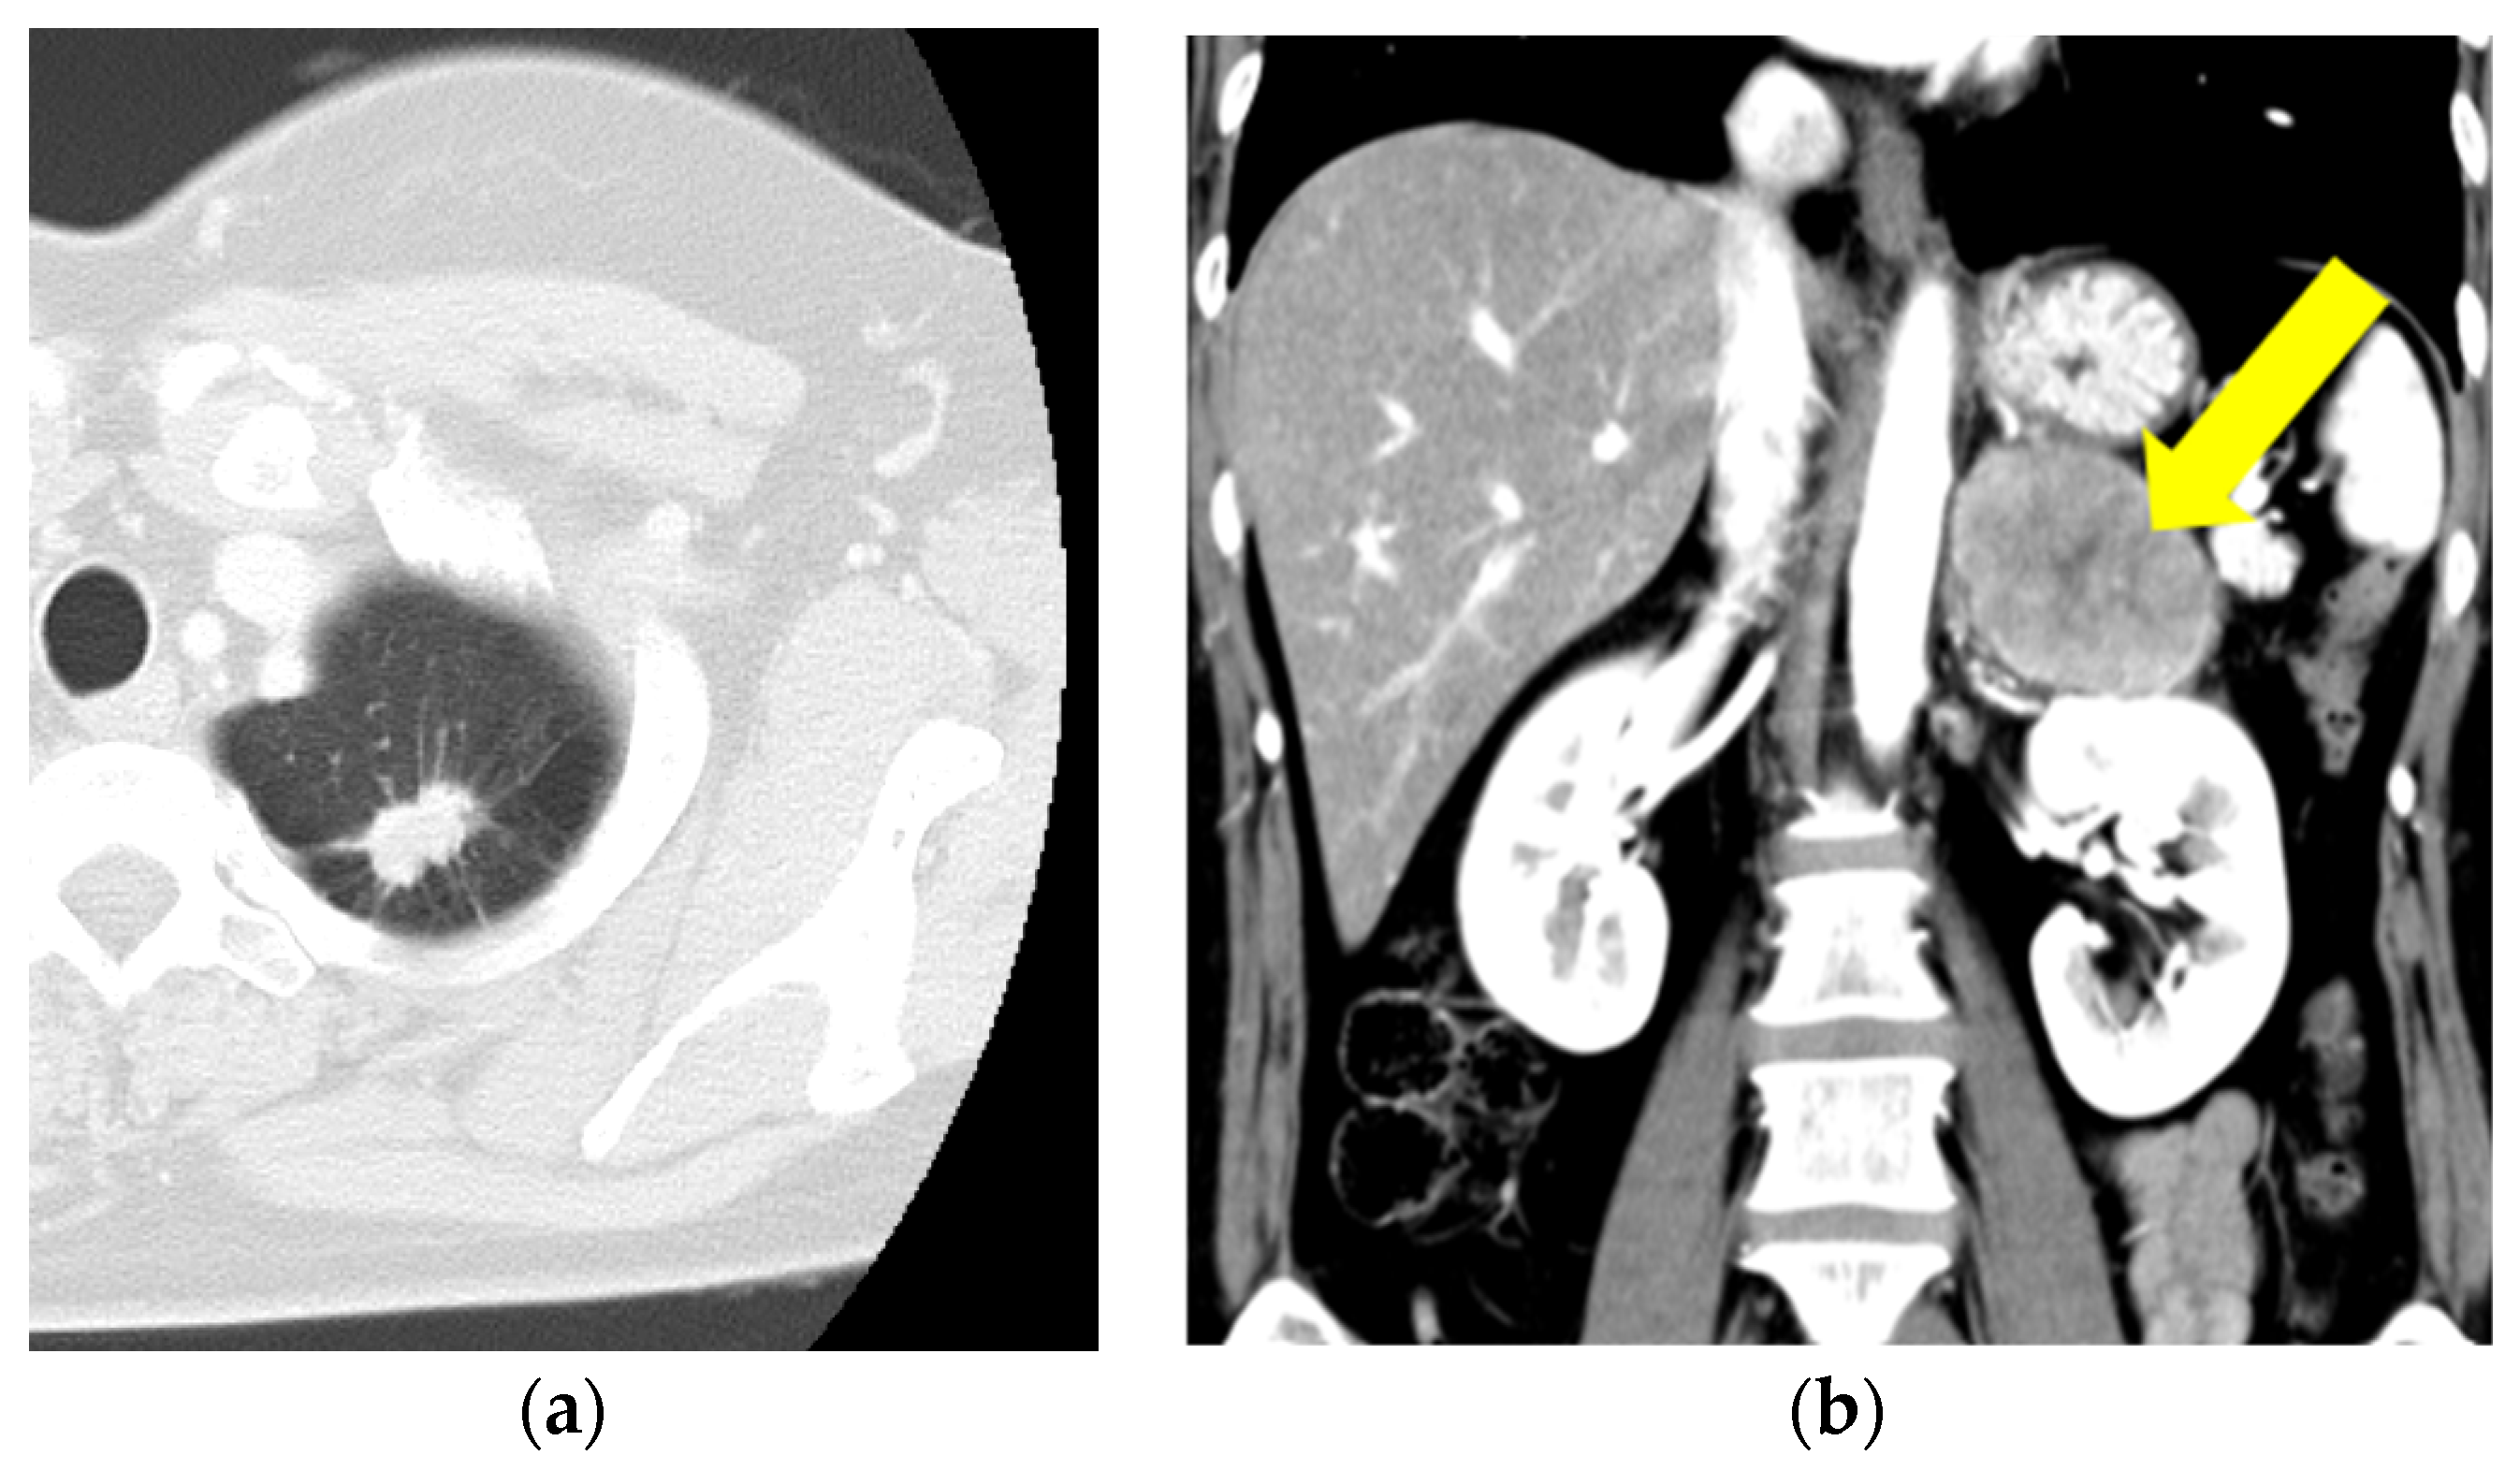

2. Case Presentation